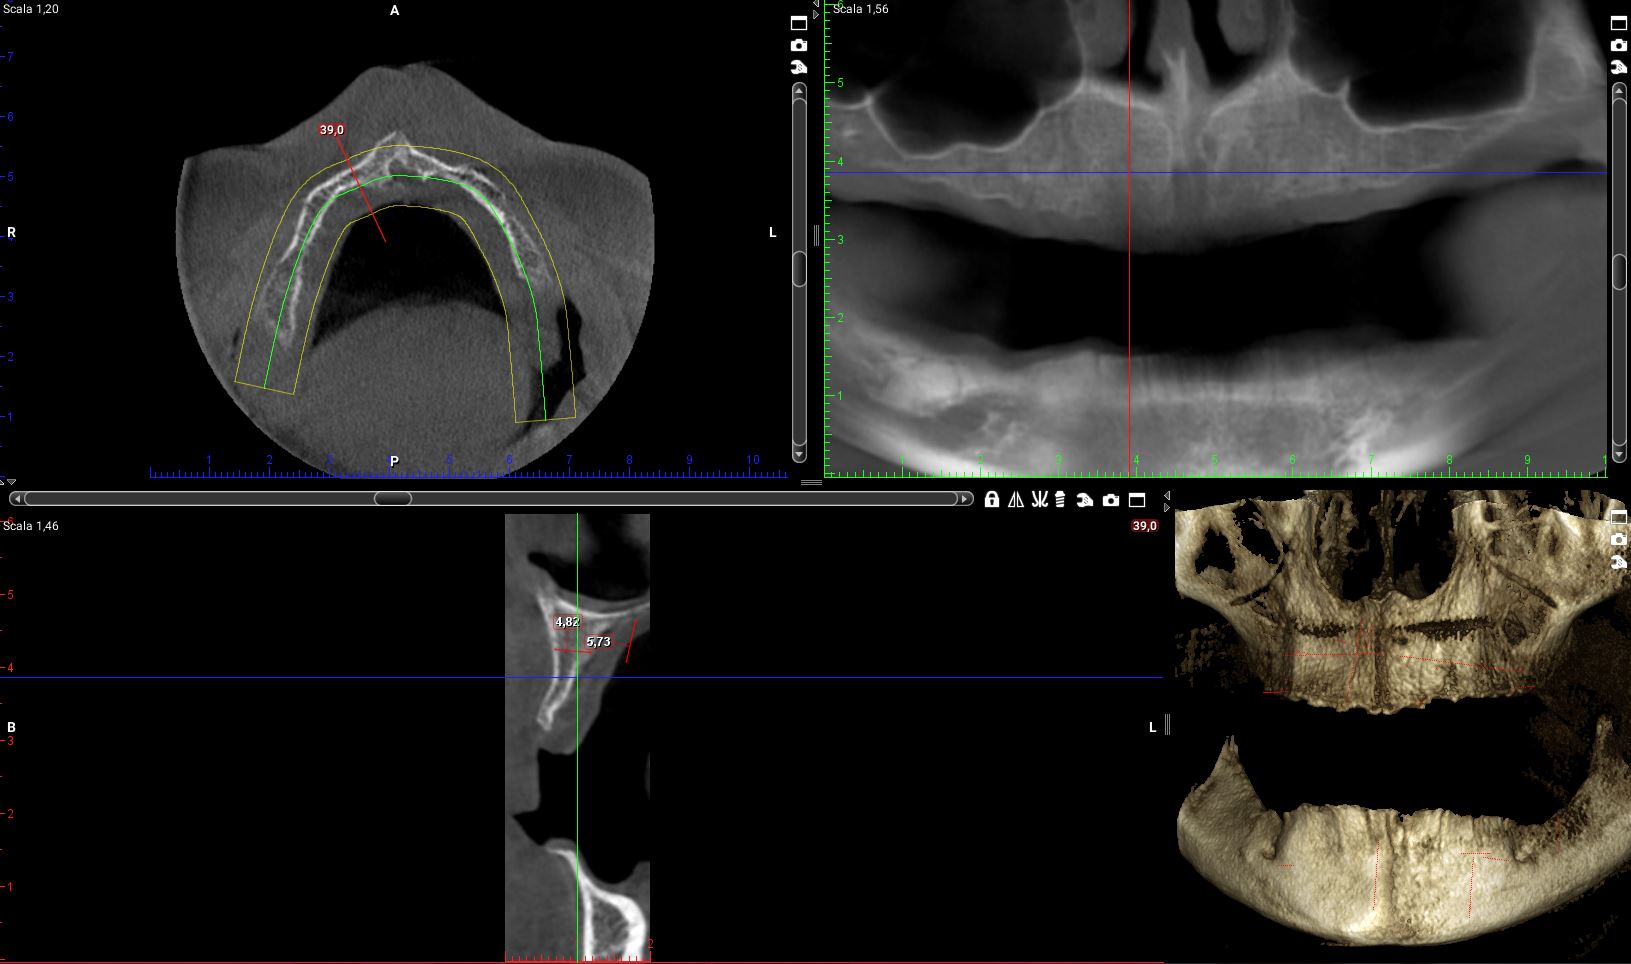

Ora riprendiamo i tagli della cone-beam della mia paziente in corrispondenza delle zone dove dovrò posizionare i quattro impianti.

Impianto distale di destra:la cresta è larga molto meno di 4mm per tutta la sua estensione in altezza. E di lì l’impianto ci deve passare!

il programma di progettazione, che tra l’altro fornisce una bella area di sicurezza intorno al volume della fixture, dice “NON SI PUO”!

Impianto mesiale di destra:

se vogliamo ricercare uno spessore di cresta che superi i 4 mm dobbiamo andare a 5mm dal pavimento del naso. Io non farei un carico immediato full-arch su un impianto da 5mm!

Anche qui il programma di simulazione dice “NON SI PUO’”!

Sulla sinistra e pure peggio!

Cosa ho fatto io, invece con la mia paziente!?

Ti faccio vedere.

Eppure l’osso non c’era!!!! O almeno così aveva detto l’interpretazione rigida della simulazione al computer.